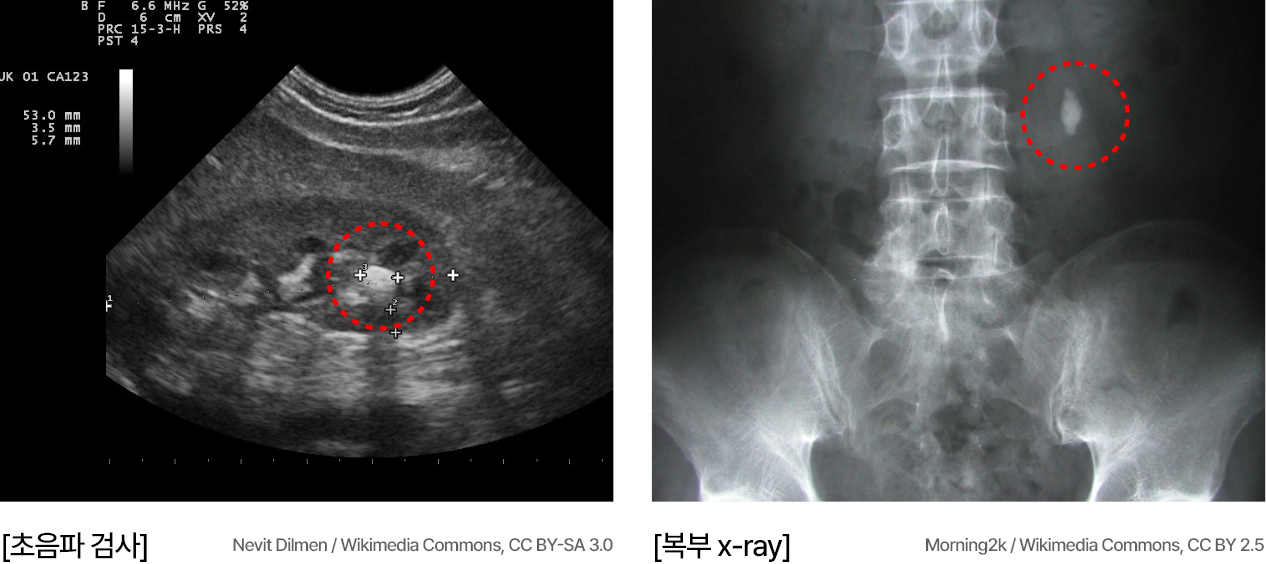

요로결석은 신장, 요관, 요도, 방광 등 요로 기관에 단단한 돌(결석)이 생겨

통증을 유발하는 대표적인 비뇨기 질환입니다.